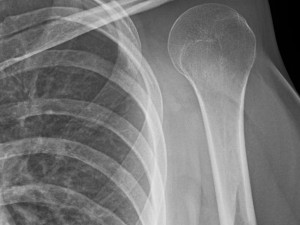

Paceintem svatoananeských lékařů byl teprve třiadvacetiletý mladík, jemuž před rokem odstranili celou lopatku pro nádor. Šlo se o levou končetinu s těžkým funkčním omezením a těžkým kosmetickým defektem. Mladík měl de facto nepoužitelné rameno - jeho pohyblivost byla nulová, protože hlavice pažní kosti se neměla o co opřít. Vzhledem k mladému věku pacienta se tak lékaři rozhodli jít do rozsáhlé implantace ramenního kloubu včetně lopatky.

„Operace trvala 3 hodiny, jednalo se o složitou operaci, navíc v ČR jedinečnou. Bylo nutné vypreparovat zádový sval a jím překrýt umělou lopatku,“ sdělil Tomáš Tomáš. „Náhrada lopatky byla pro pacienta vyrobena na míru, je z titanu a postříbřená z důvodu minimalizace infekce. Je vyrobena pomocí 3D tisku," doplnil.